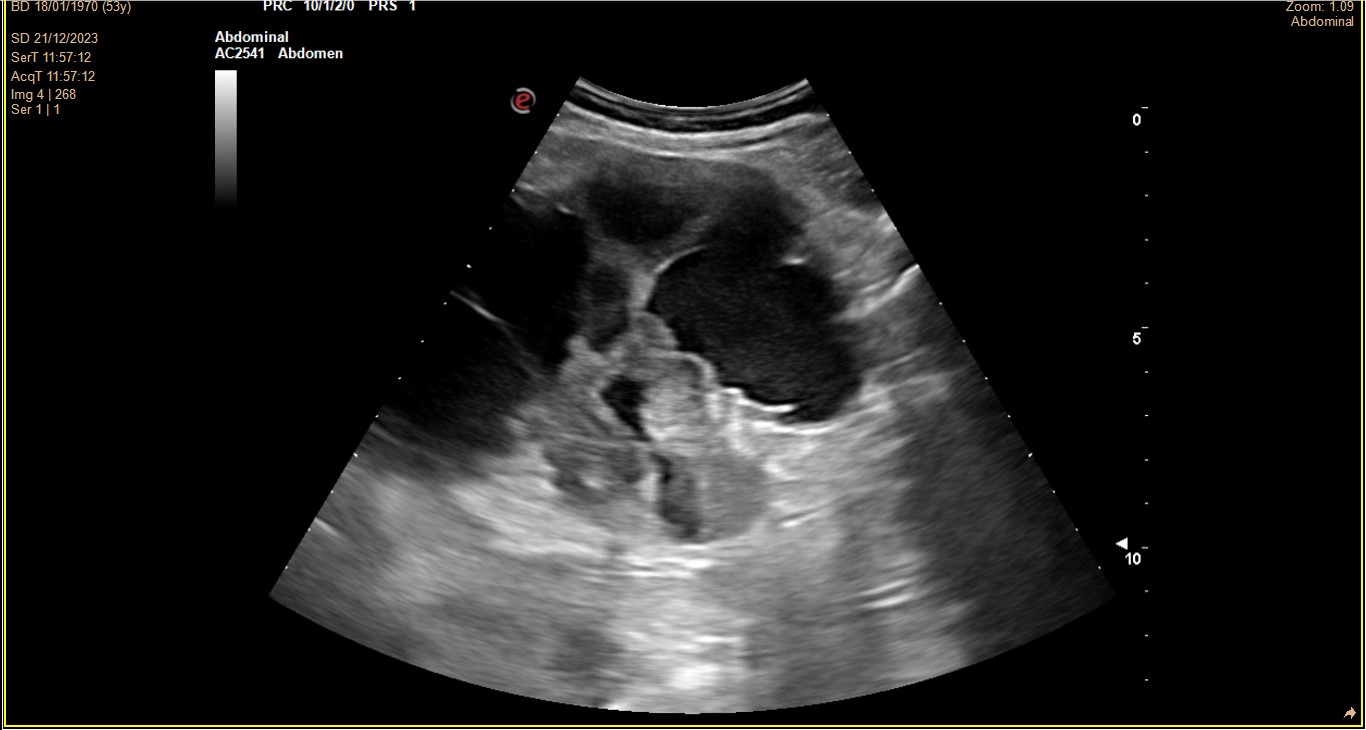

Dolor y nàuseas controladas con metamizol, come poco. Mal control glucémico. FG 87.7, Creatinina: 0,78, Urea 41,3. Pido estudio orina y función renal + ECOAP urinària en consulta: imagen hidronefrosis grado 4 RD vs imágenes anecoicas múltiples sin contenido, limites conservados pero desestructurades.

Derivación UHR (contacto telefónico). Ecografía Rx hospital. RD: Ecoestructura heterogénea. Diferenciación corticomedular alterada. Alteración morfológica. Dilatación hidronefrosi grau IV. No aumento de vascularización. RI: No se observan alteraciones.

TC 15 días. Enfisema paraseptal y centrilobulillar. Renal derecha neoformación hiperdensa en pelvis y uréter con coágulos, atrofia parenquimatosa, dilatación urétero-pielo-calicial sin litiasis. Hígado cúpula con calcificación periférica, valorar quiste hidatídico.